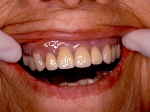

両側5歯症例 主訴-義歯のバネが壊れて手前の歯が痛んできた。 術前(旧義歯装着、鏡像)

術前(下顎粘膜面、鏡像)